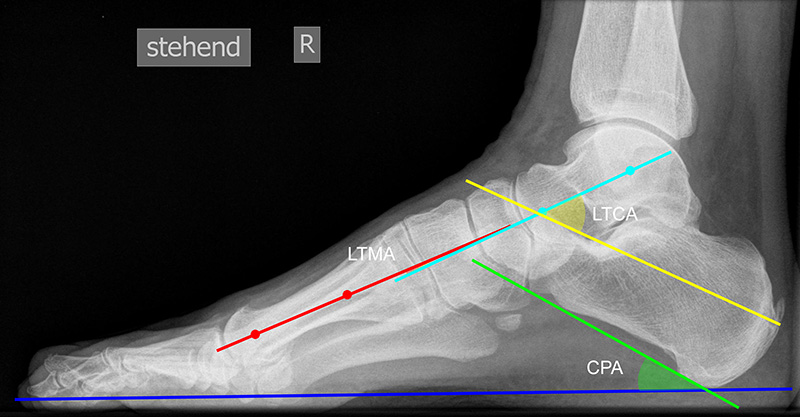

Beurteilung von Fehlstellungen des Mittel- und Rückfußes

Zur Vollansicht und zum Lesen der Bildbeschreibung bitte die Bilder anklicken.

Achsen auf der lateralen Aufnahme

Die Grundlinie (blau) ist definiert durch den tiefsten Punkt der Sesambeine und den tiefsten Punkt des Kalkaneus.

CPA (Calcaneal pitch angle): Der Kalkaneus Inklinationswinkel liegt zwischen der Grundlinie (blau) und der plantaren Begrenzung des Kalkaneus (grün) (Norm 20,8 ± 4,1° 11, 15-39° (Zwipp 2014)).

LTCA (Lateral talocalcaneal angle): Der laterale talokalkaneare Winkel liegt wird gebildet aus der Talusachse (türkis) und einer Verbindungslinie zwischen dem Oberrand des Proc. ant. Calcanei und der dorsalen Begrenzung des Kalkaneus (gelb). (Norm: 33° Range 25-45°) 1213).

LTMA (Lateral talometatarsal angle, Syn. Meary’s angle): Der laterale talometatarsale Winkel wird gebildet aus der Achse des Os metatarsale I (rot) und der Achse des Talus (türkis). (Norm: 7,1 ± 10,8 11).